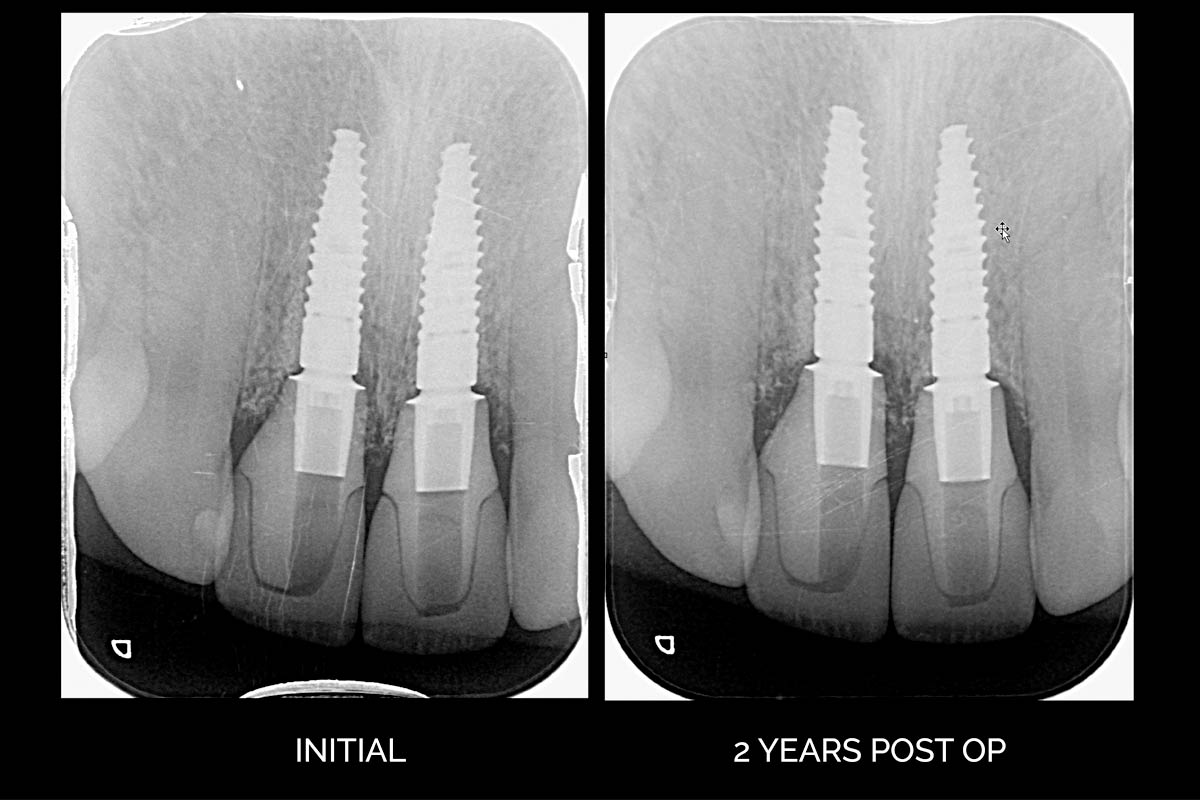

11/12 - X-ray initial and two years post-op

Treatment of a double root fracture in the aesthetic zone with cerabone® – Dr. J. M. Abarca